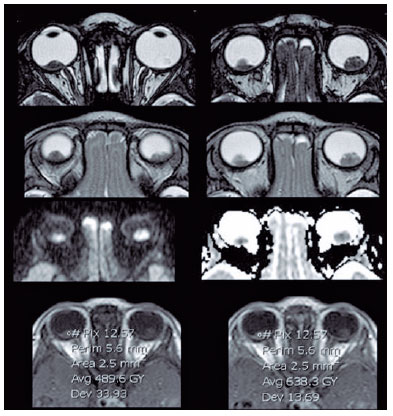

In addition, the ADC values of the 8 eyes were evaluated, and the mean was 0.615 × 103 mm2/s. The mean ADC value of poorly or undifferentiated retinoblastoma was 0.520 × 103 mm2/s, whereas in differentiated tumors, the mean was 0.774 × 103 mm2/s (Table 3).

In accordance with previous studies, our results also showed lower ADC values in poorly differentiated retinoblastomas with a mean of 0.520 ×103 mm2/s, whereas in well and moderately differentiated, the mean was 0.774 × 103 mm2/s. Cui et al. evaluated the ADC values of 53 eyes with retinoblastoma and observed lower ADC values in poorly or undifferentiated retinoblastoma (0.74 ± 0.13 × 103 mm2/s2) than those of well-differentiated (0.91 ± 0.14 × 103 mm2/s) (p<0.002)(13) (Figure 4).

Razek et al. also found that the mean ADC value was significantly different between well-differentiated (0.54 ± 0.20 × 103 mm2/s) and moderately differentiated retinoblastomas (0.51 ± 0.07 × 103 mm2/s) compared with poorly differentiated (0.44 ± 0.07 × 103 mm2/s) and undifferentiated retinoblastomas (0.41 ± 0.01 × 10-3 mm2/s)(4).